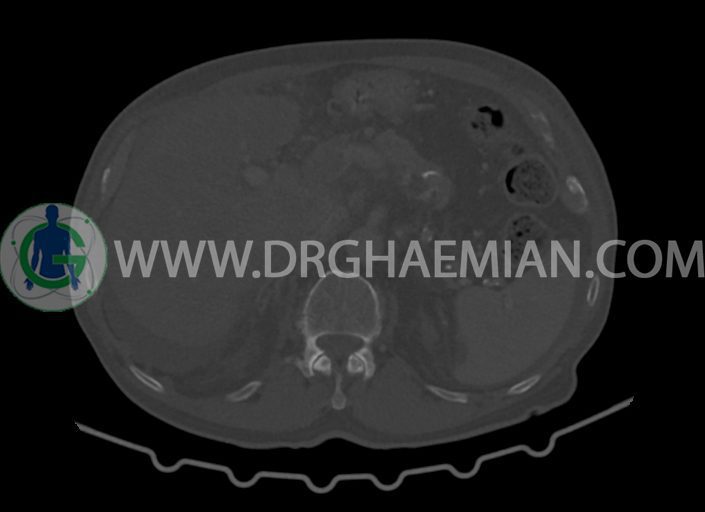

در سی تی اسکن اسپیرال شکم و لگن با کنتراست خوراکی و وریدی (مولتی دیدکتور 16 با مقاطع ظریف و بازسازی های ساژیتال و کرونال) :

-کیست های کورتیکال ساده در هر دو کلیه به بزرگترین قطر 27mm در سمت چپ (بوسنیاک 1)

-کلسیفیکاسیون آئورت شکمی و شاخه های آن

-لنف نودهای متعدد بعضا با مرکز نکروزه به شرح زیر رویت شد:

-به بزرگترین SAD=14mm در گاستروهپاتیک

-به SAD=10mm در زنجیره سلیاک

-چند لنف نود به بزرگترین SAD=16mm در محور SMA